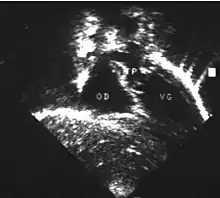

- L'échocardiographie qui est de plus en plus l'examen pratiqué en première intention. Cet examen permet d'affirmer le diagnostic en montrant les anomalies anatomiques, d'apprécier le caractère plus ou moins fonctionnel des shunts cardiaques fœtaux, de rechercher d'autres anomalies associées et dans une certaine mesure d'apprécier le retentissement de la malformation.

- Les coupes échographiques les plus utiles à cette fin sont :

- la coupe parasternale gauche grand axe : elle montre que le vaisseau issu du ventricule gauche (le plus postérieur) se dirige anormalement vers l'arrière et se bifurque précocement. C'est donc le tronc pulmonaire et non l'aorte comme normalement ;

- les coupes sous costales qui montrent bien le trajet parallèle des gros vaisseaux et leur inversion.